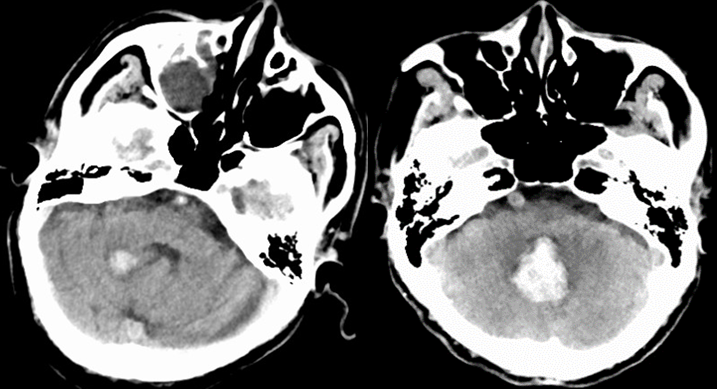

小脑出血小脑半球出血(左图),小脑蚓部出血(右图)

责任血管:多为齿状核动脉破裂

病因:高血压动脉硬化,小脑血管畸形,动脉瘤

症状体征: